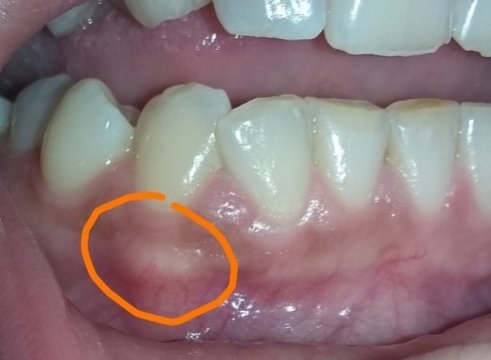

Подскажите, пожалуйста. Болела десна около недели, незначительно. Позже образовался какой-то шарик, похожий на прыщик. А после, во время еды что-то стало мешать и вот появилось непонятное новообразование из десны. На ощупь твердое, беспокоит во время приема пищи.

Подскажите, что это может быть?

Очень сложно определить, но все Ваши симптомы говорят и свищевом выходе. То есть, на верхушках зуба имеется воспалительный процесс.